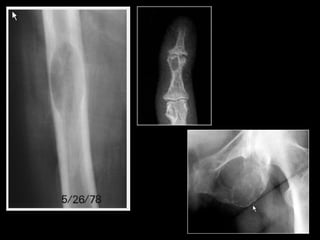

A, AP radiograph of the knee in a 2-year-old girl with rickets shows generalized osteopenia and widening of the metaphyses of the proximal tibia and fibula. B, AP radiograph of

the wrist in another child with rickets shows generalized osteopenia, as well as widening and irregularity of the metaphyses of the distal radius and ulna.

Rickets in a young child with growth plate widening and irregularity in the wrist (A) and knees (B). Note the small epiphyses in the knees.

• The M/C radiologic sign is generalized

• Increased lucency, widening, elongation,

irregularity, and cupping of the metaphyses.

– Earliest; Slight axial widening of the physis

– Next; Increased lucency of the zone of provisional

calcification.

– More advance; The physis widens and its contour

becomes irregular.